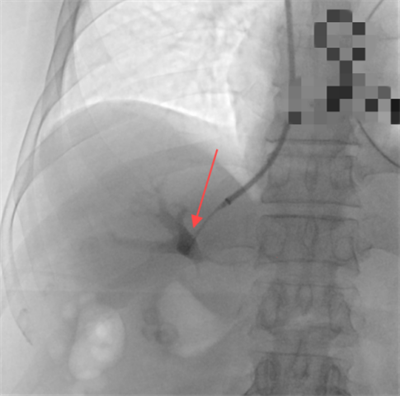

图一:肝穿刺针成功进入肝门静脉

随后,赵扬程介入手术团队决定为患者施行经颈静脉肝内门体分流术(TIPS),术中经颈静脉入路精准植入8毫米覆膜支架,于肝静脉与门静脉间构建分流通道,同步完成食管胃底曲张静脉栓塞。术后门静脉压力由36厘米水柱降至20厘米水柱,出血立即停止,血红蛋白水平稳定回升。该手术在有效降低血管压力的同时维持肝脏血流灌注,为患者争取到后续治疗的宝贵时间窗。